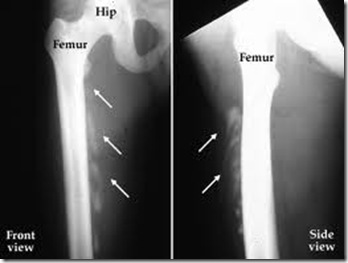

No one understood what caused the abnormal bone growth, so there was no treatment. But now, research from Northwestern University Feinberg School of Medicine and the Perelman School of Medicine at the University of Pennsylvania shows that a neuropeptide in the brain called Substance P appears to trigger the formation of the extraskeletal bone. Eliminating Substance P prevents the bone growth.

In the paper, Kan reports that knocking out Substance P in animals prevented the development of the extraskeletal bone in an animal model.

“This work establishes a common mechanism underlying lesion induction for nearly all forms of heterotopic ossification including brain and spinal cord injury, peripheral nerve injury, athletic injury, total hip replacement and FOP,” said paper co-author Frederick Kaplan, the Isaac & Rose Nassau Professor of Orthopaedic Molecular Medicine at Penn’s Perelman School. “These novel findings usher in a new era in understanding of these complex disorders.”